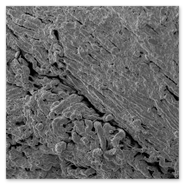

1. Scanning Electron Microscopy Processing unit

Electron Microscopy (EM): Basically two types:

1. Transmission Electron Microscope2. Scanning Electron Microscope

1. Transmission Electron Microscope (TEM) processing unit2. Scanning Electron Microscope (SEM) processing unit3. Ultra Microtome and Histopathology4. Experience in the field of specimen preparation for past 16 years